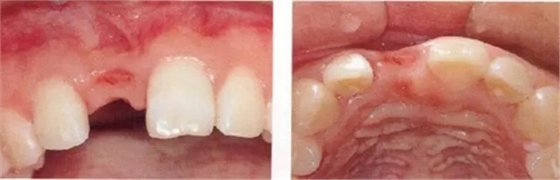

▲圖44-7,8

7個月后,牙齦組織的愈合狀態(tài)。